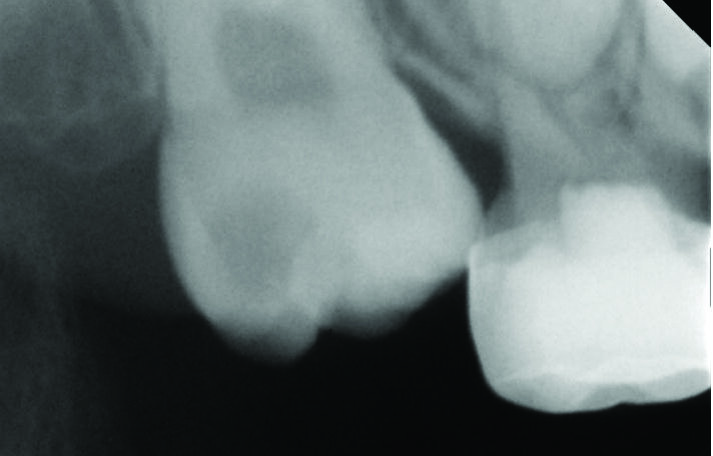

Figure 2: A periapical radiograph showing ectopically erupted upper right first permanent molar.

Ectopic eruption of the first permanent molar occurs due to the abnormal mesioangular eruption path of the molar resulting in an impaction at the distal prominence of the primary second molar’s crown. It can be suspected if asymmetric eruption is observed or if the mesial marginal ridge is noted to be under the distal prominence of the second primary molar. Ectopic eruption can be diagnosed from bitewings or panoramic radiographs, Fig 1, 2. The prevalence of this condition is reported to be up to 0.75%1. The ectopic eruption is more common in cleft lip and palate patients1.